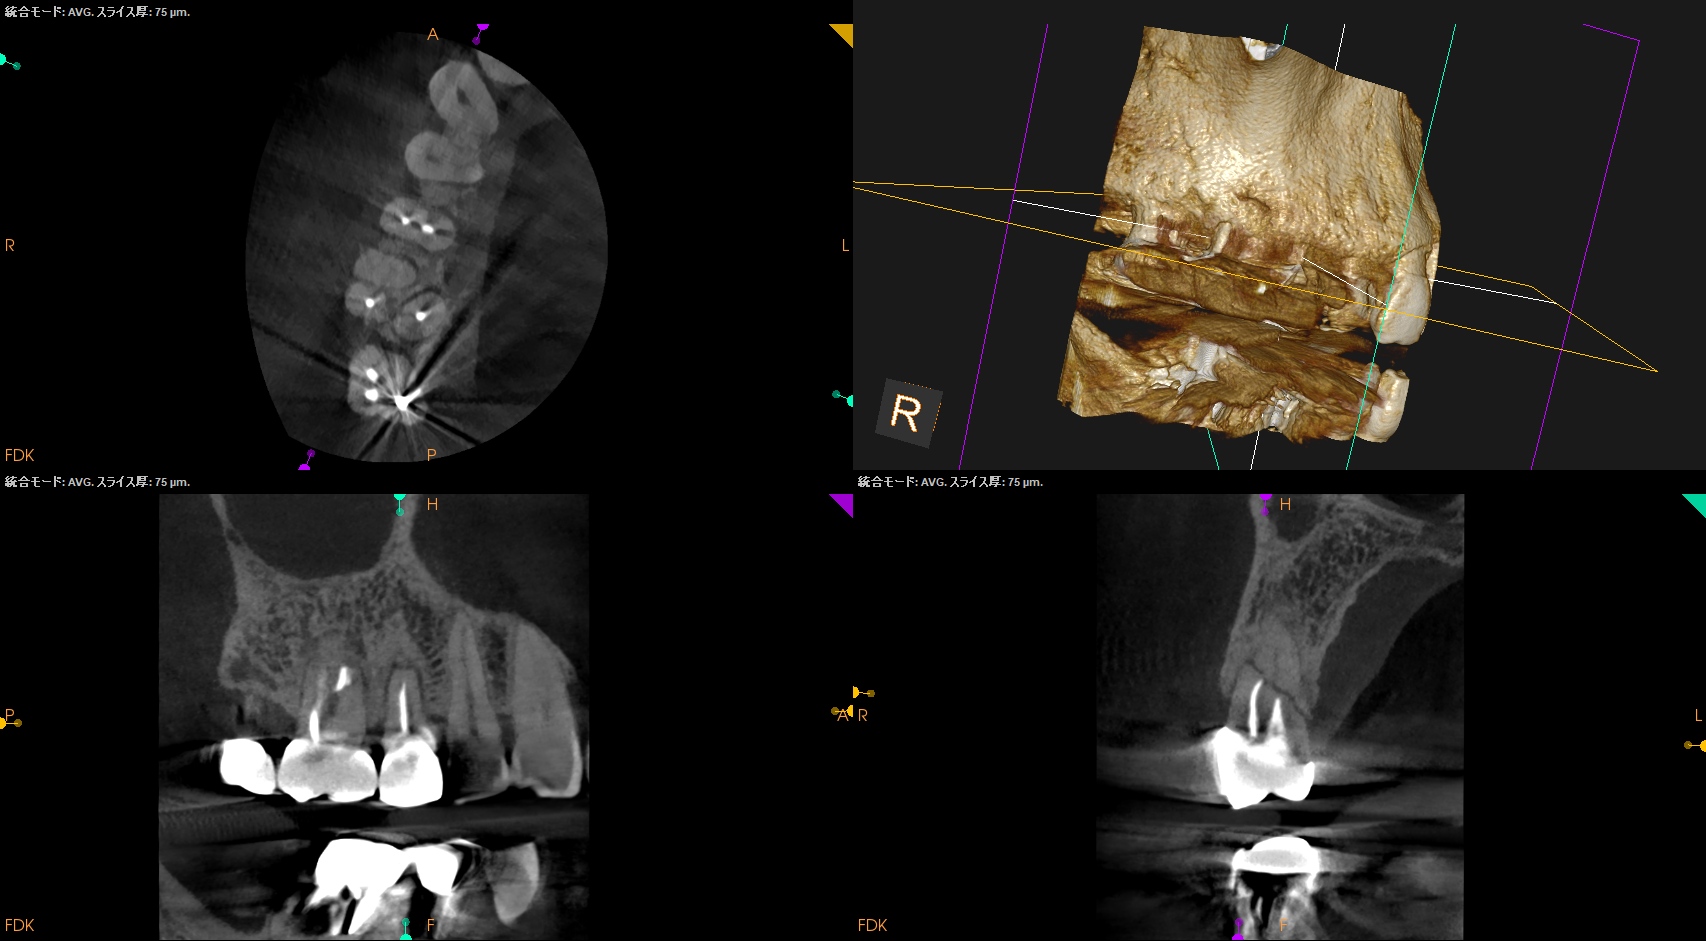

CBCT(2024.10.28)

#4

歯根の中央で水平に破断している。

ここで重要なことは破折片の口蓋側寄りの歯根には病変がないということだ。

ということは…

そこは根管治療が不要である。